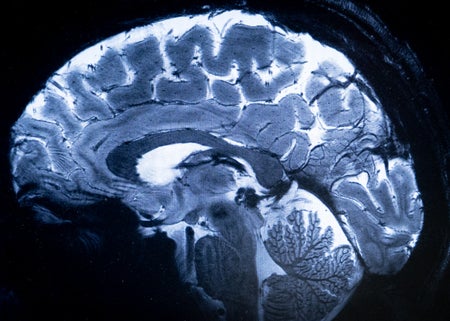

Where Does Consciousness Come From? Two Neuroscience Theories Go Head-to-Head

Two leading theories of consciousness went head-to-head—and the results may change how neuroscientists study one of the oldest questions about existence

Scientists Identify a Brain Structure That Filters Consciousness

Our conscious awareness may be governed by a structure deep in the brain

Consciousness Might Hide in Our Brain’s Electric Fields

A mysterious electromagnetic mechanism may be more important than the firing of neurons in our brain to explain our awareness